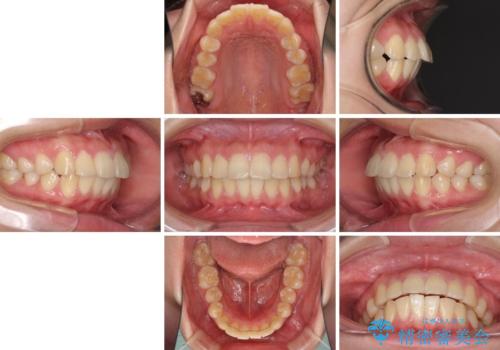

部分矯正で出っ歯になった 出っ歯改善の抜歯矯正

- 上下前歯を部分矯正したところ出っ歯になってしまったとのことで来院された患者様です。

上下左右第一小臼歯4本を抜歯して、積極的に口元を引っ込めるよう、ワイヤー装置にて矯正治療を行うこととしました。